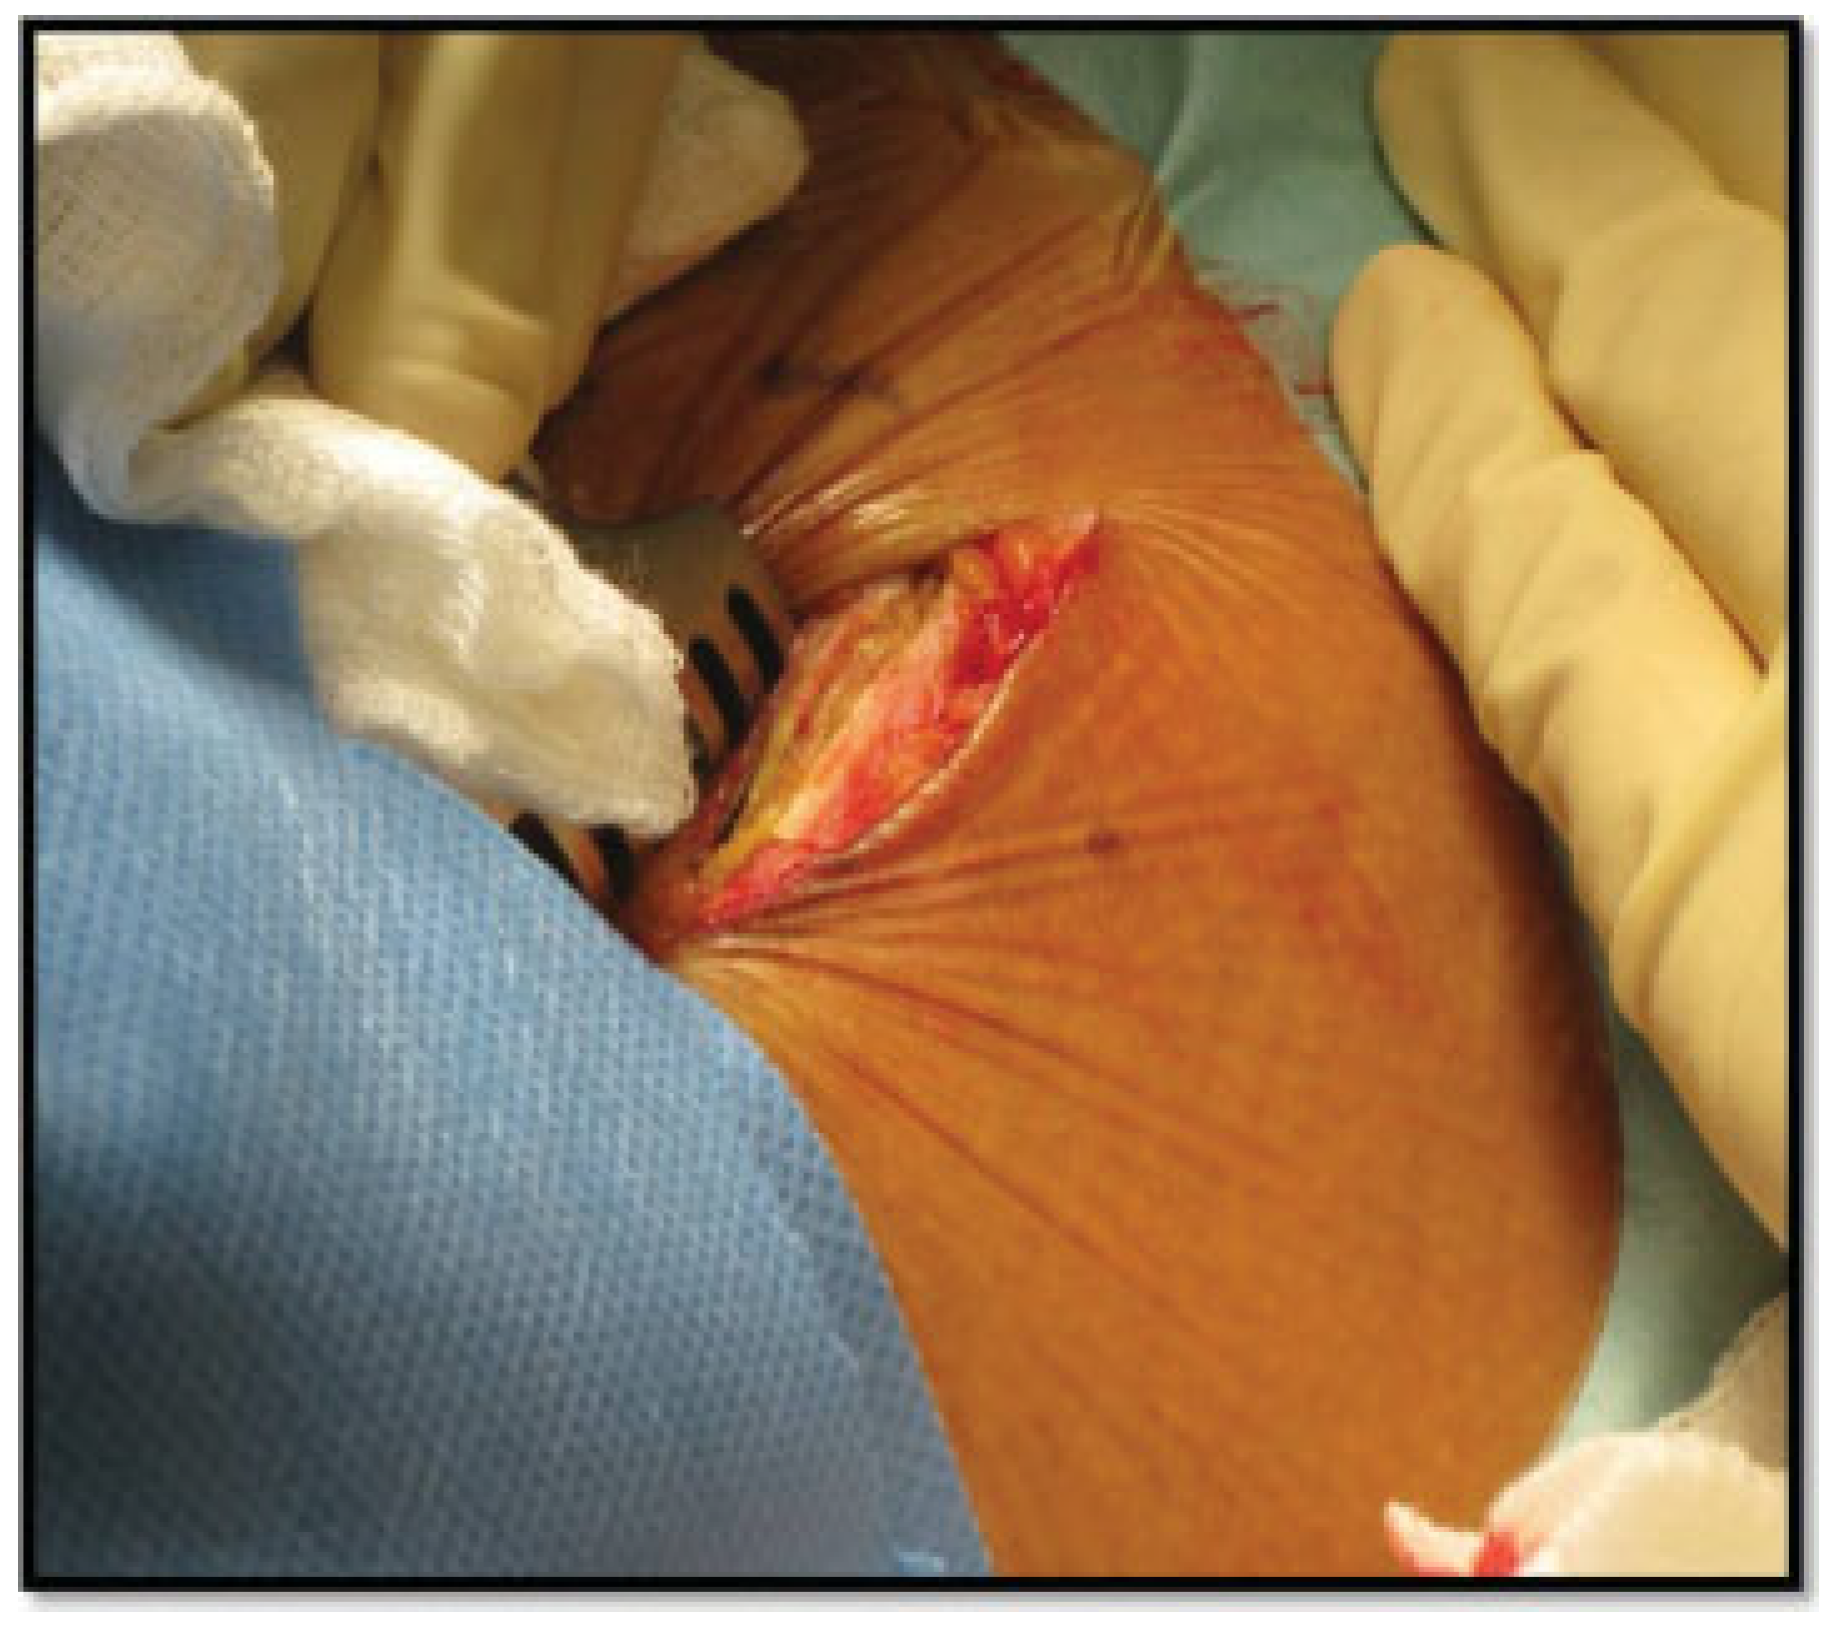

Surgical Technique